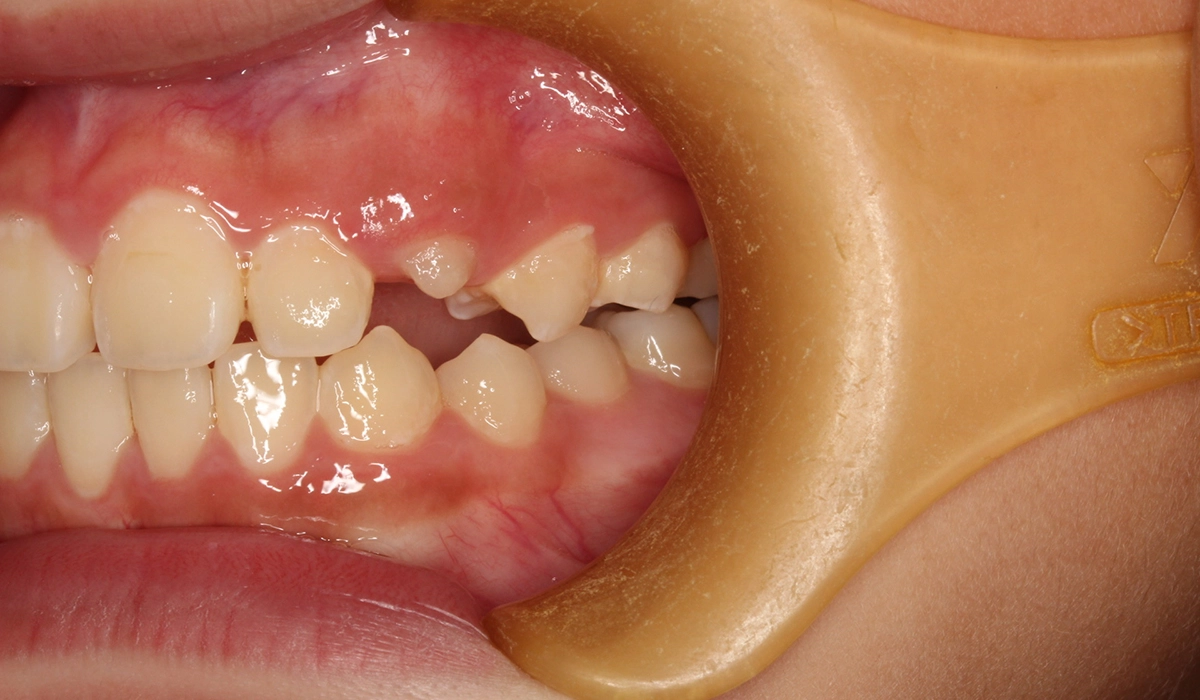

術前:右側

術前:左側